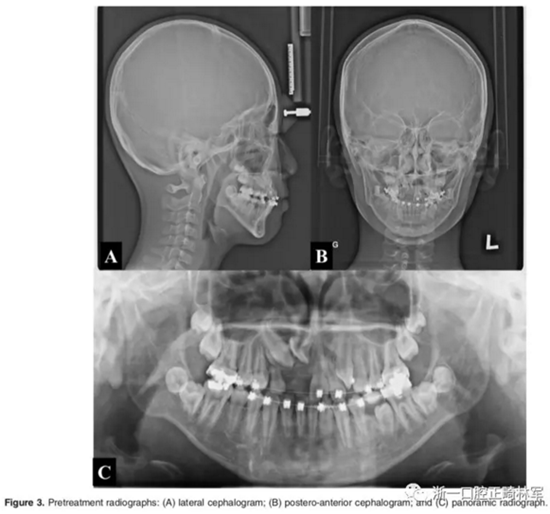

影像檢查:

全景X片及CBCT示:11-13復雜阻生,上頜前牙區(qū)牙槽骨水平不足;11阻生,遠中旋轉(zhuǎn)90°,牙冠朝向腭側,根尖位于鼻底、前鼻棘皮質(zhì)骨內(nèi),牙根形態(tài)彎曲;12、13不完全易位,12位置偏腭側,13位置偏舌側,12的牙根形態(tài)也較彎曲。

診斷:骨性I類,牙性II類,高角,多牙阻生,面部不對稱(右偏),上下切牙直立。

影像學:頭顱側位片示:矢狀向和垂直向骨骼發(fā)生變化(ANB角,3°;SN-MP,51°);上頜切牙略前傾(U1-SN,106°),與下頜切牙一致(IMPA,75°);病人的面部輪廓得以保持。全景片示:由于牙齒萌出,上前牙區(qū)垂直向牙槽骨水平增加;雖然前牙牙根較彎曲,但其平行度仍可,且無明顯的牙根吸收。CBCT示:前牙唇側骨質(zhì)連續(xù)性改善,牙根唇側支持組織變好,牙槽骨高度、厚度均有增加,但轉(zhuǎn)矩的改變一定程度上導致了局部應力的增大。